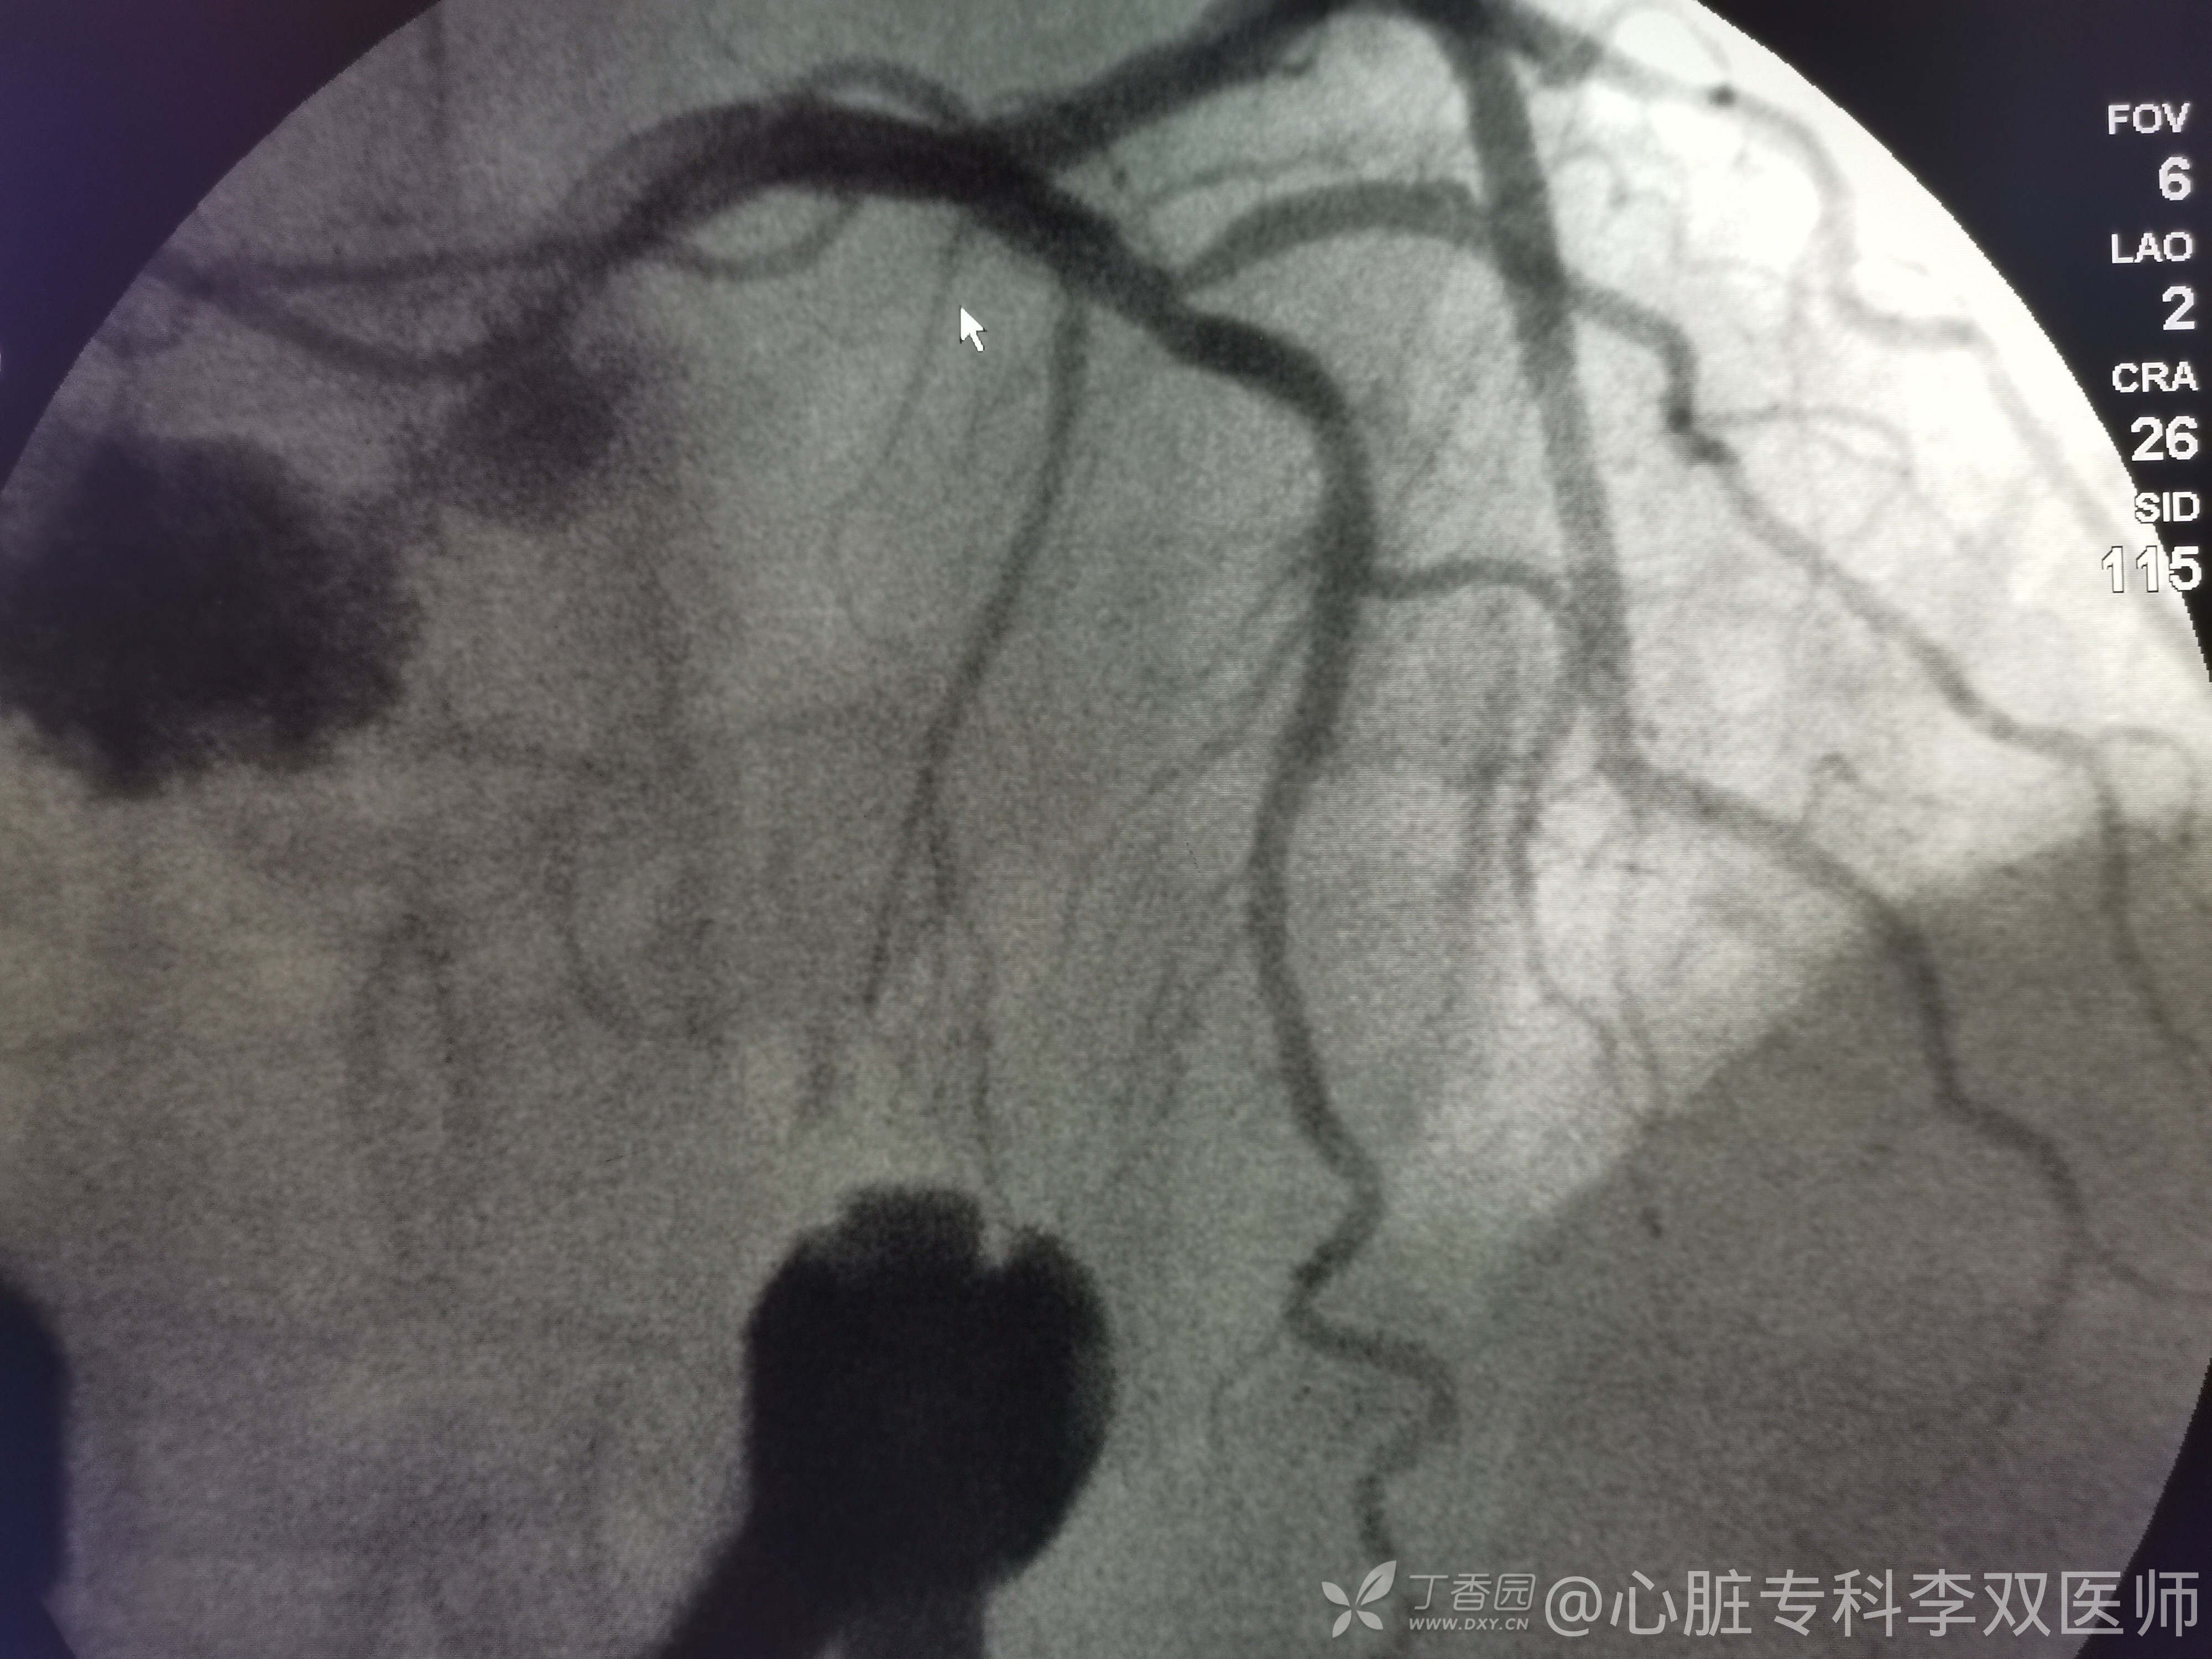

前天看走眼了个心电图,如下:

6.5收治到某内科(非心内科),在缓冲病房住满72小时候转到普通病房。生化等无特殊,尤其多次查心肌酶(6.5、6.8、6.11)不高。因胃肠镜需要停用抗血小板药物,后偶然查心电图如上(这也是她唯一一份心电图,不要问我为什么入院这么多天才做心电图,不清楚)。

我们会诊考虑确实不能排除心梗,当时做了急诊冠脉造影,不是心梗!(彩超没有报室壁瘤,不过它也排除了血栓,所以才敢打心室造影的)。

心尖部大室壁瘤引起的前壁和侧壁ST抬高,推测患者20年前放支架是急性前壁心梗。